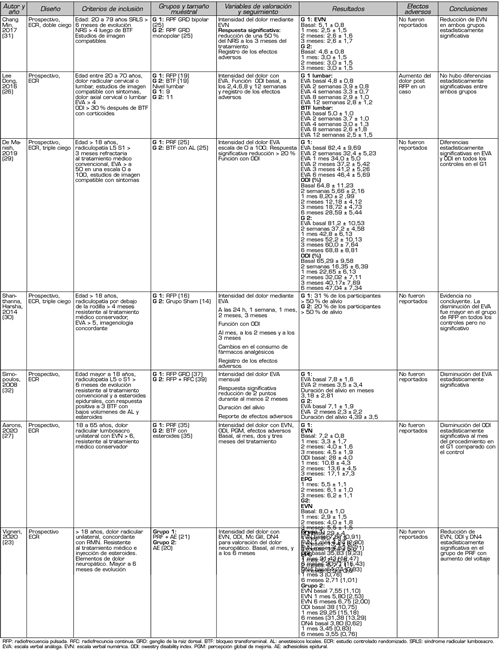

En la presente búsqueda bibliográfica se encontraron ocho estudios prospectivos randomizados (23,26-32), y nueve de diseño cuasiexperimental (33-41), de tipo antes y después, evaluando la eficacia de la RF del GRD. Es de destacar que, en los primeros, existe una alta heterogenicidad clínica en relación con el grupo control utilizado como comparador, así como a otras intervenciones utilizadas antes y después del procedimiento evaluado (por ejemplo, esteroides o anestésicos locales epidurales) (Tabla I). Esta heterogenicidad complica la interpretación de los resultados e impide la adecuada realización de un metanálisis (3). La Tabla II muestra los parámetros utilizados en la aplicación de radiofrecuencia pulsada, en los ocho estudios prospectivos randomizados.

Tabla I. Estudios controlados randomizados para medir eficacia y perfil de seguridad de RFP del GRD

Lee y cols. (2016) comparan los efectos de la RFP del GRD con los de inyección transforaminal de esteroides en 20 pacientes con dolor radicular lumbosacro divididos en 2 grupos de 9 y 11 pacientes respectivamente (26).

Utiliza la Escala Visual Análoga (EVA) y el Índice de Discapacidad de Owestry (IDO) como evaluadores de resultados durante un periodo de tres meses, encontrando una mejoría en dichas escalas cuando se comparan con las medidas basales, pero sin encontrar diferencias estadísticamente significativas entre los procedimientos evaluados (26).

Arons y cols. (2020) también utilizan la inyección transforaminal de esteroides como grupo control para evaluar el efecto analgésico en de la RFP del GRD en pacientes con dolor radicular lumbosacro unilateral (27). Los autores realizan un estudio randomizado, doble ciego y controlado, en 70 pacientes divididos en dos grupos de 35, utilizando en el grupo de estudio la RFP del GRD durante 180 segundos, siendo las variables estudiadas el efecto global percibido (EGP), la Escala Verbal Numérica (EVN) y el Índice de Discapacidad de Owestry, evaluados a los 30, 60 y 180 días. Los procedimientos eran repetidos a los 30 días en aquellos pacientes en los cuales la mejoría se encontraba por debajo de un 50 % en relación a los valores basales. Los autores econtraron una mayor reducción de la discapacidad en el grupo tratado con RFP del GRD en la evaluación a los 30 días, en comparación al grupo tratado con inyecciones de esteroides, mientras que a los 180 días el porcentaje de pacientes que presentaban mejoría del dolor era levemente mayor en este grupo que en el tratado con RFP (67 % versus 60 %). En este estudio no se registraron complicaciones (27).

Koh y cols. (2015) estudiaron los efectos de agregar la RFP del GRD a la inyección epidural transforaminal de esteroides en 62 pacientes con dolor radicular lumbosacro refractarios a tratamientos no intervencionistas, en dos grupos de estudio de 31 pacientes cada uno (27). En ambos grupos se realizó la inyección de 20 mg de triamcinolona posteriormente a la realización de 3 ciclos de 120 segundos de radiofrecuencia pulsada o de una simulación de la misma (grupo “sham”). Si bien los autores encontraron mejoría en todos los parámetros evaluados (Escala Verbal Numérica o EVN, Efecto Global Percibido, Indice de Discapacidad de Owestry) cuando se comparan los resultados obtenidos después del tratamiento con las medidas basales, no encontraron diferencias estadísticamente significativas cuando comparaban ambos grupos durante el periodo de control de 3 meses. Sin embargo, si se ajustaba al cero los resultados basales obtenidos con la EVN, la disminución obtenida a los 3 meses era mayor en el grupo donde se realizó la RFP del GRD (p = 0,038) (28).

De y cols. (2019) realizaron un estudio triple ciego prospectivo randomizado, utilizando como grupo control activo la inyección transforaminal de 1 ml de bupivacaína al 0,5 % y como grupo de estudio la realización de RFP del GRD en tres ciclos durante 180 segundos (29). Cincuenta pacientes con dolor radicular lumbosacro resistente a tratamiento conservador (farmacológico, fisioterapéutico), con una respuesta positiva previa a un bloqueo selectivo pronóstico, fueron igualmente distribuidos en los dos grupos establecidos. Como parámetros de evaluación de resultados se utilizaron la EVA y el Índice de Discapacidad de Owestry a las dos semanas del procedimiento y a los 1, 2, 3 y 6 meses. Un 100 % de los pacientes en el grupo tratado con RFP presentaron una disminución mayor o igual a 2 puntos en la EVA y una disminución significativa en el Índice de Discapacidad de Owestry en todos los intervalos de evaluación, mientras que en el grupo control un 80 % de los pacientes lo presentaron a los 3 meses y solo el 28 % a los 6 meses. Los autores concluyeron que la aplicación de 180 segundos de RFP en el GRD determina mejoría en la intensidad del dolor y mejora en la capacidad funcional de los pacientes con dolor radicular lumbosacro a medio plazo, cuando la realización previa de un bloqueo selectivo pronóstico con anestésicos locales es positivo, descartando a los pacientes no respondedores (29).

Shanthanna y cols. (2014) realizaron un estudio prospectivo doble ciego, utilizando como grupo control una simulación del procedimiento o grupo “Sham”, en los cuales se colocaron cánulas de radiofrecuencia en los neuroforamenes, incluso con estimulación sensitiva y motora, pero sin realizar finalmente la RFP, constituyendo un verdadero grupo placebo (30). En el grupo de estudio por otra parte, se realizó un ciclo de RFP durante 120 segundos, utilizando agujas de 0,5 cm de punta activa. Los autores encontraron una disminución en la EVA en todos los intervalos de evaluación (1 día, 1, 2 y 3 meses) pero sin alcanzar significación estadística entre grupos. En este estudio, el número de pacientes fue bajo, 16 en el grupo tratado con RFP y 15 en el grupo control, lo que les llevó 15 meses en obtener el reclutamiento. Debido a la escasa diferencia en el porcentaje de pacientes que experimentaron una reducción mayor o igual a 50 % de la EVA entre los grupos, los autores decidieron interrumpir el estudio por ser excesivo, de acuerdo con su criterio, el tiempo necesario para finalizar el reclutamiento. En este estudio no fue realizado una selección previa de acuerdo con la respuesta a los bloqueos selectivos con anestésicos locales (30).

Vigneri (2020) randomizó dos grupos de pacientes: en 21 realizó RFP del GRD durante 240 segundos y aumentó el voltaje entre 65 y 80 y después administró hialuronidasa, anestésicos locales y betametasona, mientras que el grupo control recibió solo la adhesiolisis y se simuló la RFP (23). Encontró que el grupo en el que se realizó la RFP hubo una reducción significativa de la Escala Visual Numérica al mes y a los 6 meses de realizado el tratamiento. Si bien el aumento del voltaje podría tener un impacto positivo en el resultado analgésico final, son necesarios nuevos estudios con más cantidad de pacientes y con un diseño que permita valorar la performance del aumento del voltaje como única variable (23).

Por último, existen estudios que comparan entre sí distintas modalidades de radiofrecuencia aplicadas sobre el GRD. Simonopulus y cols. (2008) realizaron un estudio prospectivo randomizado en 76 pacientes con dolor radicular lumbosacro crónico refractario a tratamiento convencional, distribuyéndolos en dos grupos: uno tratado con RFP del GRD únicamente, y el otro grupo tratado con el mismo procedimiento seguido de radiofrecuencia continua (32). El autor no encontró diferencias estadísticamente significativas en la disminución de los puntajes en la EVA entre los grupos, a los dos meses de realizados los procedimientos. Interesantemente, no encontró complicaciones neurológicas en el grupo en el cual se utilizó radiofrecuencia continua (32).

Chang y cols. (2017) realizaron un estudio prospectivo randomizado para comparar la modalidad de RFP pulsada del GRD unipolar (con una sola cánula) versus bipolar, mediante la colocación de dos cánulas de radiofrecuencia próximas al GRD (31). Los pacientes reclutados eran portadores de dolor radicular lumbosacro refractario a la inyección transforaminal de esteroides. Los autores encontraron una disminución de la intensidad del dolor medido por el EVN al mes, dos y tres meses de los procedimientos, siendo mayor la disminución del dolor en el grupo tratado con la modalidad bipolar (p = 0,037). Una producción de campos eléctricos de mayor intensidad y más densos en este grupo se propone como explicación para el mayor efecto analgésico (31).